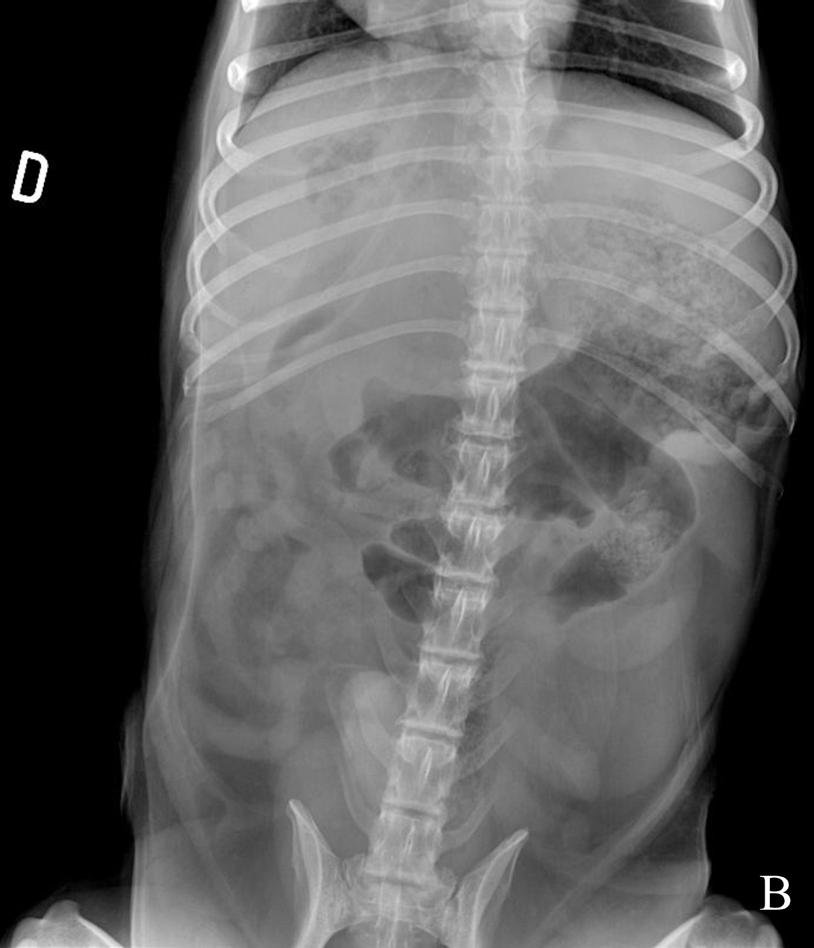

Se realizó un estudio radiográfico de abdomen con proyecciones lateral izquierda y ventrodorsal (Fig. 1).

Figura 1. Radiografías de abdomen de un perro mestizo de 12 años en proyección lateral izquierda (A) y proyección ventrodorsal (B).

Describe las alteraciones radiográficas observadas

Se observa una disminución de la visualización de las serosas abdominales en el abdomen craneal y medio (Fig. 2), con presencia de pequeñas burbujas de gas libre caudoventral a la silueta hepática compatible con neumoperitoneo (Fig. 2A). Ambas proyecciones mostraban una hepatomegalia con bordes redondeados excediendo levemente el arco costal, con presencia de una zona de opacidad gas, de morfología y bordes irregulares, poco definidos, localizada en la zona de proyección hepática en su aspecto craneoventral y con lateralización hacia la derecha (Fig. 2). Así mismo, se apreció otra lesión, de opacidad gas y de menor tamaño, caudalmente a la previamente descrita, en la zona media del hígado y asociada a un efecto masa en la proyección ventrodorsal, que producía hacia caudal un desplazamiento del cuerpo gástrico y antro pilórico (Fig. 2B). Como hallazgo incidental, se observó una espondilosis ventrolateral deformante en la columna lumbar.

¿Cuáles son los diagnósticos diferenciales compatibles con los signos radiográficos observados?

La pérdida de diferenciación de serosas fue compatible con un leve volumen de líquido libre abdominal o inflamación peritoneal, sin poder descartar otras causas como una carcinomatosis/sarcomatosis peritoneal. Las causas más comunes de neumoperitoneo incluyen heridas penetrantes, fuga de gas de órganos enfisematosos, perforación o rotura de órganos que contienen gas debido a traumatismos, neoplasias o ulceraciones y por causas iatrogénicas, (p. ej., laparotomías).1 La lesión localizada en la proyección hepática más cranealmente y lateralizada hacia la derecha con contenido gas, según su localización, podría ser compatible con un absceso hepático, colecistitis enfisematosa, neoplasia o granuloma hepático infectado. La lesión localizada más caudalmente y con efecto masa a nivel gástrico podría corresponderse con otro absceso o con la presencia de una masa necrosada de origen benigno (p. ej., hiperplasia nodular, quiste, hematoma) o maligno (p. ej., carcinoma hepatocelular).

Ante el conjunto de los hallazgos radiológicos encontrados, la sospecha principal fue de una rotura de un absceso/neoplasia hepática necrosada.